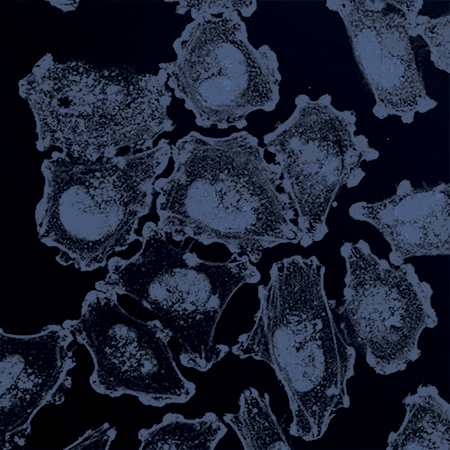

HOW MODERN DRIED BLOOD SPOT TECHNOLOGY IS HELPING COMBAT HIV

SPOT ON SCIENCES’ HEMASPOT HELPING WHA ELIMINATE HEPATITIS B AND C